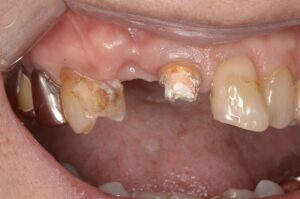

抜歯後です。だいぶ凹んでいます。